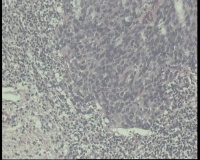

请老师 看看,宫颈活检,宫颈CINIII累腺局灶早期浸润还是直接报宫颈鳞癌?

鳞状上皮全层异型增生,局灶基底膜不清,请老师看看巢状分布的是累腺还是浸润?

CIN3累腺,不排除有浸润的可能。

有浸润,鳞癌